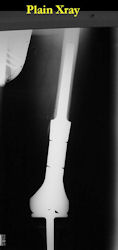

Surgery

Examples of radical limb sparing surgeries for osteosarcomas in various anatomic locations (distal femur, proximal tibia, proximal humerus, scapula)

In each case, the tumor and bone from which it arose were resected. This required meticulous dissection, mobilization and preservation of adjacent pertinent neurovascular structures. In each case presented here, the defect was reconstructed with a special modular segmental tumor prosthesis. This also replaces the adjacent joint in many instances.

| Limb-sparing surgery for osteosarcoma of distal femur – Plain Xrays |